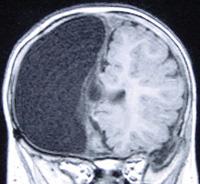

- Hemimegalencephaly, also called unilateral (one-sided) megalencephaly: This disorder affects only one side of the brain and makes it larger than the other side.